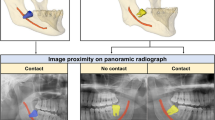

Extraction of the mandibular third molar (M3) is one of the most common surgeries in the oral and maxillofacial field [1,2,3]. Inferior alveolar nerve injury, an important surgical complication, occurs in about 0.35–8.4% of impacted M3 extractions [4]. The positional relationship between an impacted M3 and the inferior alveolar canal (MC) is the main factor that determines the risk of inferior alveolar nerve injury [5]. Panoramic radiographs have been used for preoperative imaging to predict and minimize such complications [2, 6, 7]. To predict the relationship between the M3 and the MC in panoramic radiographs, clinicians have to infer specific radiological signs (e.g., darkening or narrowing of the root, bifid apex, and interruption or diversion of the cortical outline of the MC) [8]. However, the anatomical position of the impacted M3 in relation to the MC cannot be determined easily because of superimposition and distortion of the surrounding anatomical structures in the two-dimensional (2D) panoramic radiographs [5, 9].

Cone-beam CT (CBCT) has been widely used to overcome the limitations of 2D panoramic radiographs in the oral and maxillofacial field [10]. CBCT has the advantages of lower radiation dose and cost compared with multi-detector CT, and shows three-dimensional (3D) information of anatomical structures including the teeth, jaw bone, and inferior alveolar nerve [9, 11, 12]. The 3D positional relationship between the MC and the M3 in the buccolingual direction can be determined using the cross-sectional images of CBCT. In this respect, six types of relationships were established based on the distance between the M3 and the MC, the level of contact, and the 3D positional relationship in the CBCT images [7]. The relationships were classified quantitatively based on the presence of the contact, periarticular, interradicular, buccal, and inferior positions [13]. In a previous analysis of risk factors for nerve damage with paresthesia after extraction of the M3, Wang et al. stated that the direct contact relationships between the inferior alveolar nerve and the root of the M3 as well as the buccal or lingual positions observed in preoperative CBCT images were important factors [13, 14]. Additionally, a previous study reported that the possibility of damage to the inferior alveolar nerve was higher if it was located lingually [12]. The rate of MC passage to the lingual side of the M3 root was high when the MC and the M3 were in contact [15]. Therefore, confirming the relative buccal or lingual relationship of the MC with the M3 is an essential procedure for accurate risk assessment and treatment planning to avoid or reduce inferior alveolar nerve damage during an M3 extraction.

The buccolingual relationship of the M3 and the MC was determined by analysis of successive slices in multiplanar CBCT images by an oral and maxillofacial radiologist. The passing direction and path of the MC were evaluated based on the lamina dura of the M3. If the MC directly contacted or passed in close proximity to the inner surface of the M3 root, it was considered a lingual class, but if it directly contacted or passed in close proximity to the outer surface of the M3 root, it was classified as a buccal class (Fig. 1). We excluded the CBCT images in which it was difficult to determine the positional relationship between the MC and M3 for classification dataset. In our study, the radiologist annotating the images was unaware of critical information that could bias their assessments. This information included the patient's dental history, the patient's clinical symptoms, or demographic information. When the interpreter was not aware of the patient's clinical information, they were less likely to make assumptions about the patient's condition based on that information. This could lead to a more accurate interpretation of the image.